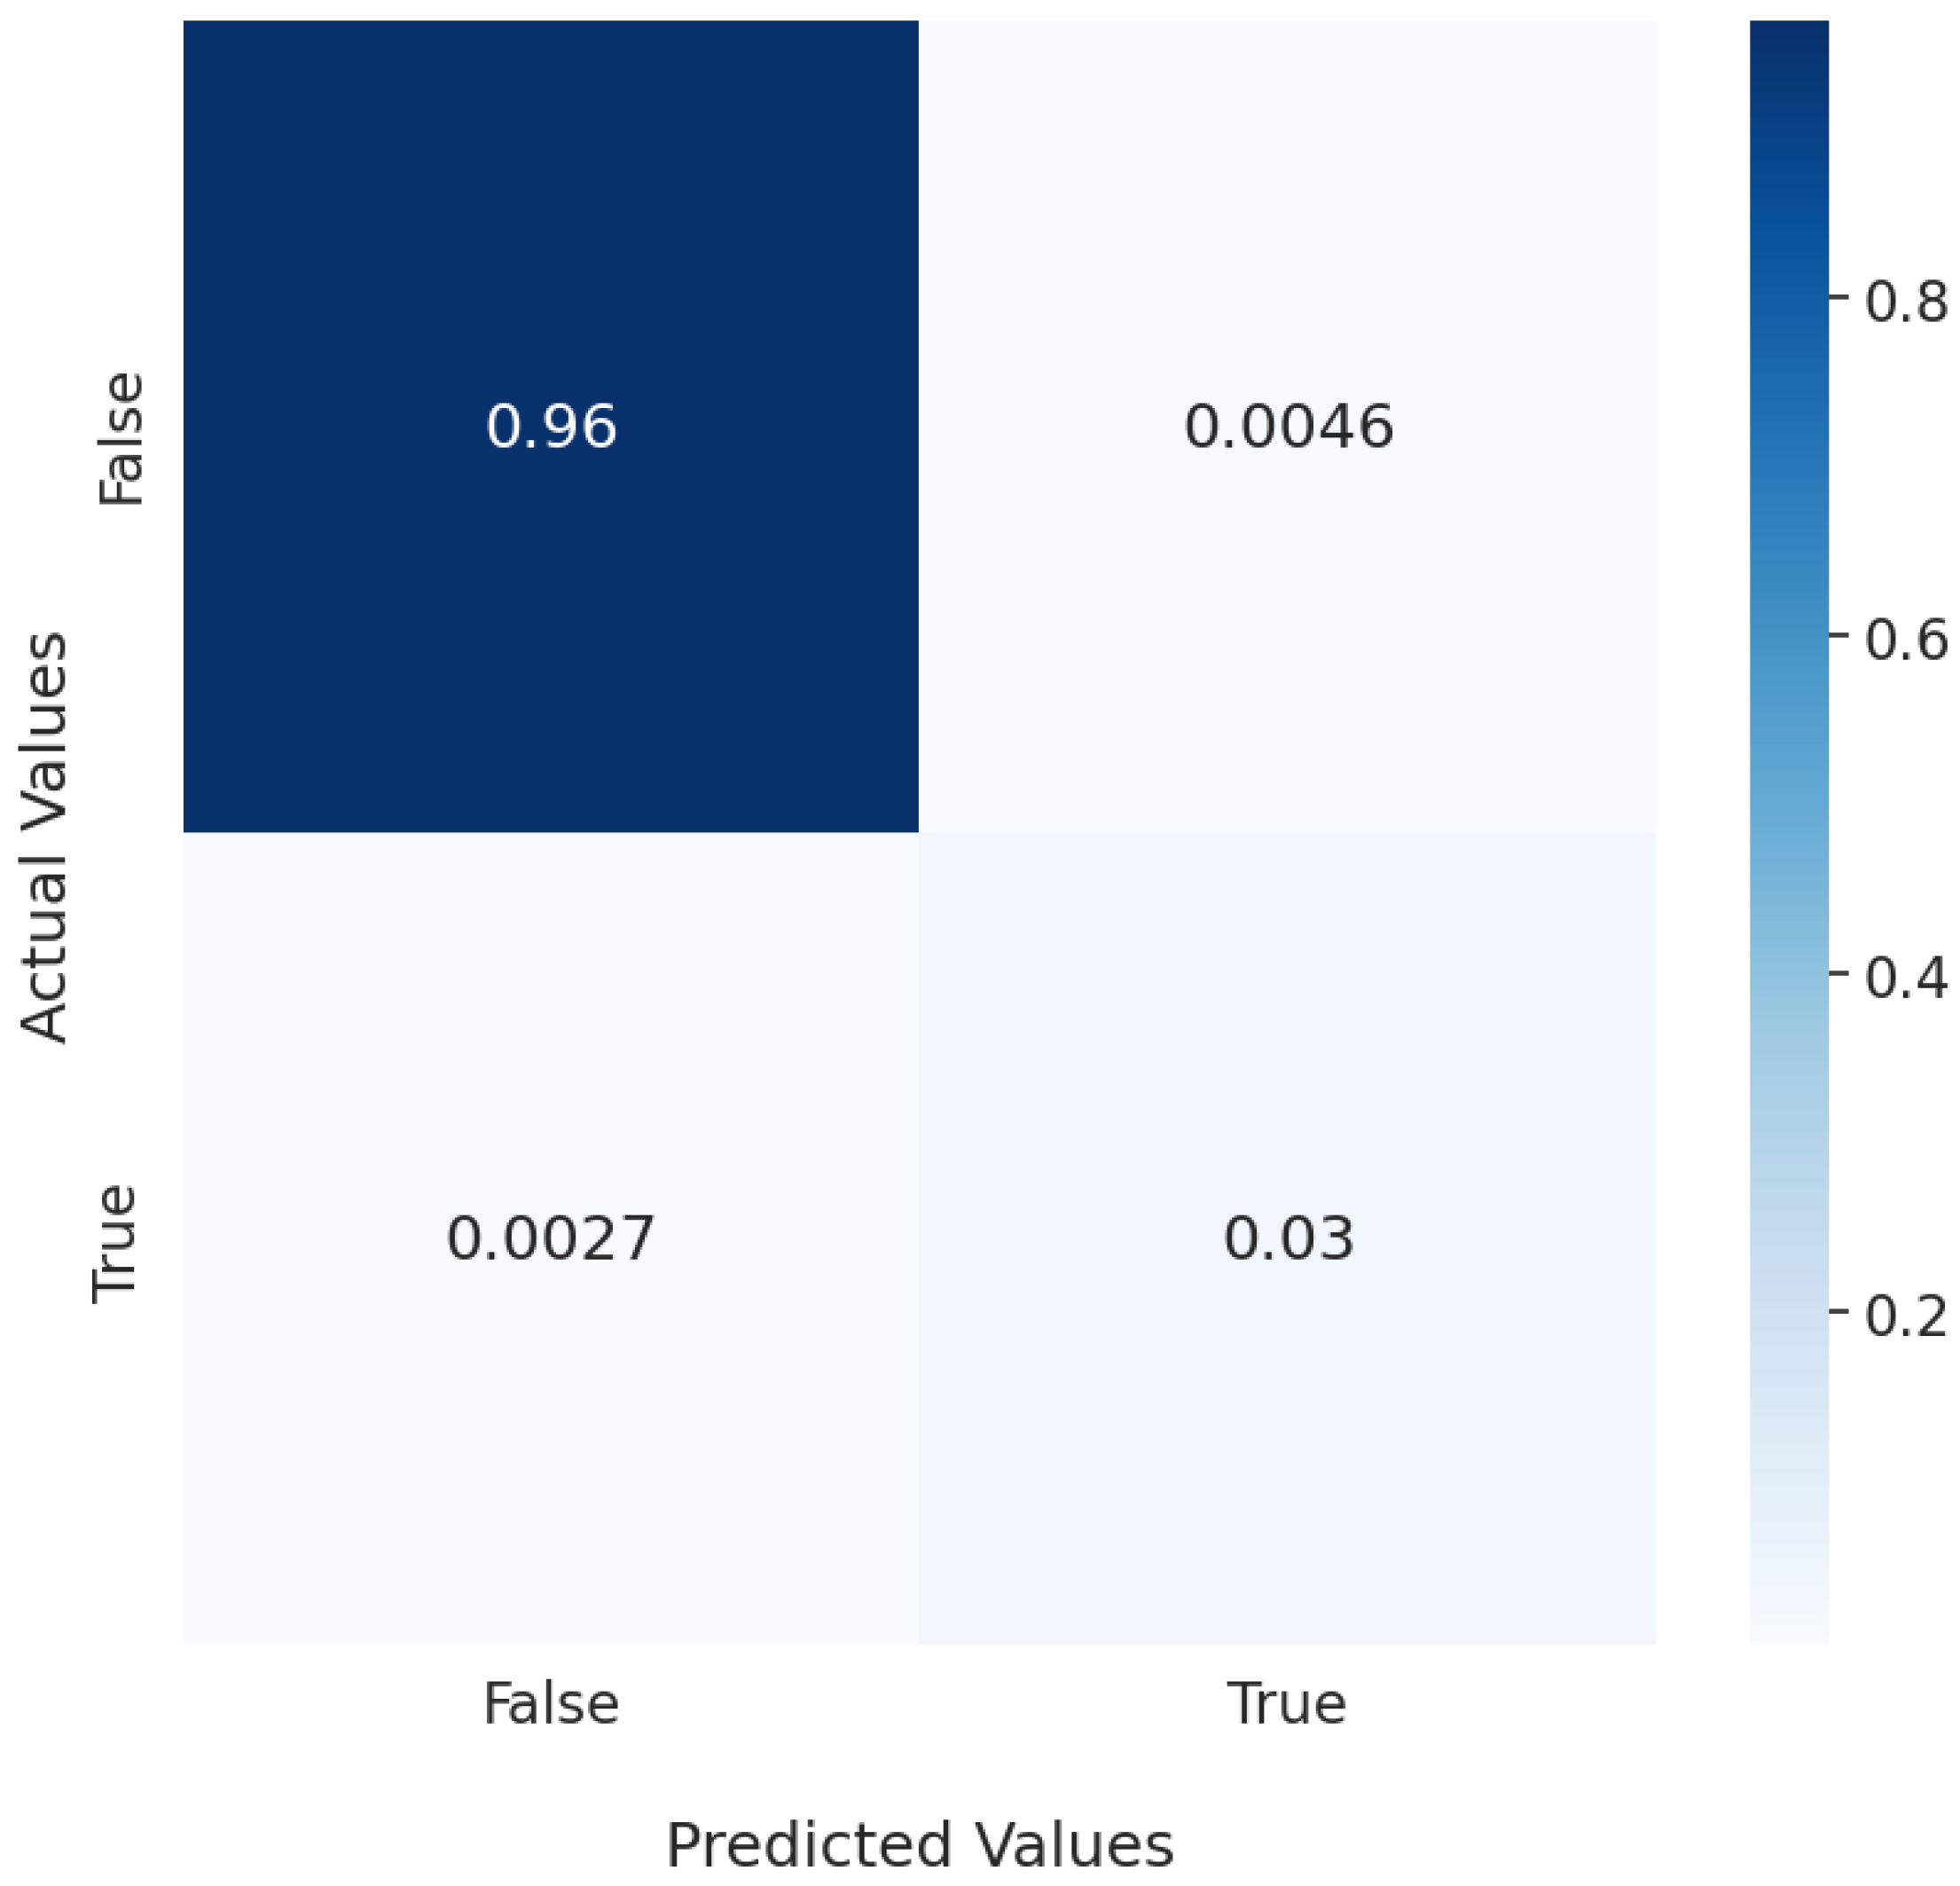

3.1. Segmentation of Vertebral Bodies from Medical Data